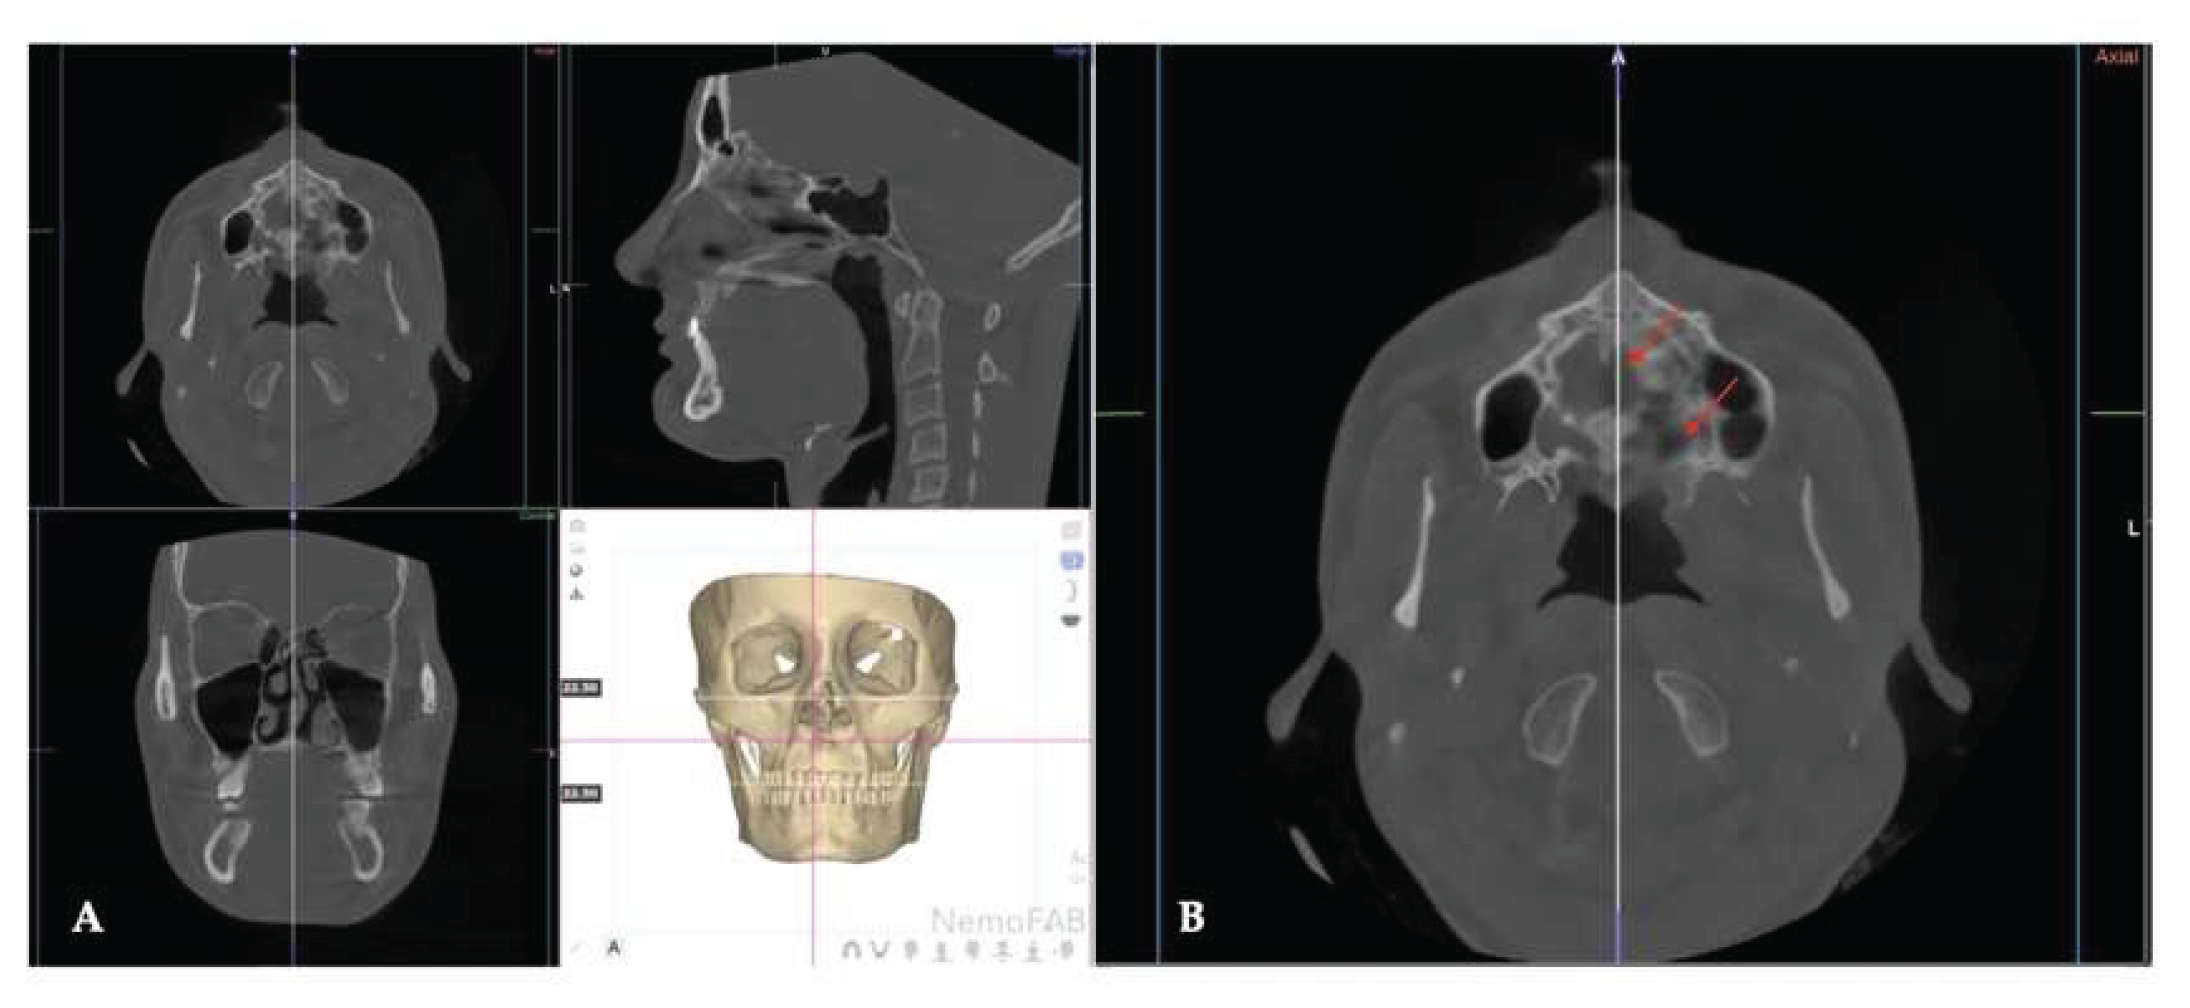

Background: While mini-screw-assisted rapid palatal expansion (MARPE) is effective for correcting maxillary transverse deficiency in adults, perimaxillary suture disarticulation—particularly at the pterygomaxillary junction—can be inconsistent. This study evaluates skeletal and dentoalveolar outcomes of a novel 3D-guided midpalatal piezocorticotomy-assisted MARPE protocol, focusing on expansion symmetry and pre-existing asymmetries. Methods: Three adult patients were retrospectively analyzed after treatment with 3D-guided midpalatal piezocorticotomy-assisted MARPE expansion and one with non-guided midpapalatal piezocorticotomy and MARPE expansion. Surgical guides were digitally designed using CBCT data to align with the nasal septum orientation in multiple planes. Perimaxillary suture disarticulation was measured pre- and post-expansion, and dentoalveolar changes were evaluated. Post-expansion asymmetries were addressed using directly printed aligners. Results: Complete midpalatal suture separation (mean 8.48 mm), involving both anterior and posterior nasal spine regions, was achieved in one patient. Bilateral pterygomaxillary disarticulation averaged 1.06–1.23 mm, resulting in forward–outward rotation of the nasomaxillary complex. Additional separation occurred at the frontonasal (2.03 mm) and vomeromaxillary (1–2 mm) sutures, with no significant changes in orbital or peri-orbital sutures. One patient presented with pre-existing dentoalveolar asymmetry, which intensified the perceived post-expansion imbalance but was successfully corrected with directly printed aligners. In the second case, 5.6 mm of suture separation resulted in a limited lateral nasal width increase (<1.5 mm), while maxillary base expansion exceeded 6 mm. A significant canine plane cant (1.2 mm) and divergent axial inclinations of the maxillary central incisors relative to the palatal plane were also observed. In the second case, a non-impactful palatal bone fracture with asymmetric displacement of the left palatine fragment was documented. After 16 months of aligner therapy, all cases exhibited favorable remodeling of the palatal structures, midpalatal suture, and alveolar processes, accompanied by improved dental alignment, occlusal plane symmetry, and mandibular dentoalveolar adaptation. The dento-alveolar expansion achieved in the third case over the course of 16 months of treatment was approximated at 4 mm. The fourth case showed consistent improvement with direct printed aligners after MARPE midpalatal diasrticulation of 11 mm after experiencing minor bone fracture. Conclusions: Human skulls exhibit considerable variability between the left and right sides, which can influence spatial balance. Pre-existing cranial asymmetries appear to be the primary contributors to asymmetry following MARPE treatment. Careful evaluation of dentoalveolar discrepancies and axial tooth inclinations is essential for preventing and managing potential asymmetric dental arch outcomes during the post-expansion phase. Although peri-maxillary bone fractures are relatively uncommon, their occurrence is influenced by multiple factors. Adjunctive techniques, such as 3D-guided midpalatal piezocorticotomy, show promise in significantly lowering the risk of intra-expansion peri-maxillary fractures.